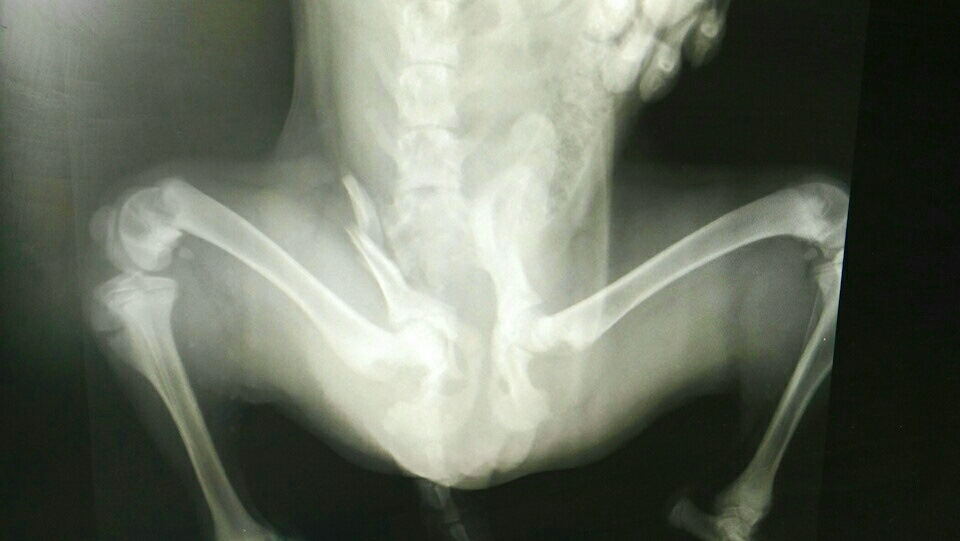

Дело так было! Ещё раз! Сегодня как обычно ехал с работы и на сахалинской какой-то збил собаку и дальше поехал! Не смог мимо проехать так как собака живая жизнеспособная извевалась среди мимо едущих людей. Там была женщина с девочкой девочка плакала-я им оставил номер и повёз на Лермонтова там сделали снимок перелом таза у щенка мне дали телефон валантера 89244820433 и привёз в кот и пёс на железнодорожный 180б.Встретили очень приятные мужчина и женщина и взяли щенка на простыню.Кто не равнодушен и может оплатить операцию и прибывания щенка позванить ей её имя Ксения. Если есть добрые люди с деньгами помогите щенку-ему плохо.Завтра будут думать что с ним делать.Большое спасибо Ксении от меня что согласилась принять щенка…Люди ну если не увидели если так вышло ну остановитесь помогите собаке что ж вы как сволочи!Видите мечется бедняга ну пропусти ты её чо не успеешь ты что ли чо давить то.Только на пасху бога боитесь? Вернётся к каждому.